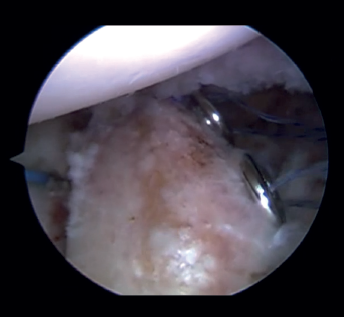

Introduction of the glenoid guide and positioning of the sheaths

(Figures 2 and 3)

Figure 2. View from the anterosuperior portal (left shoulder). Note the glenoid guide positioned at the centre of the defect and drilling at its upper and lower portion, spaced 10 mm apart.

Arthroscope is introduced through the anterosuperior portal, and the glenoid guide is introduced through the posterior portal, and passed paralel to the glenoid surface until the hook is located at the centre of the bone defect. The guide is secured with two cannulas inserted through two small accessory incisions, until connecting with the posterior cortical layer. Both cortical layers are drilled through them using a 2.8 mm drill fitted with a sheath so that on withdrawing the drill the sheath is positioned at drilling level. This step is made twice to introduce two sheaths: one above and the other below the glenoid guide hook and spaced 10 mm apart. Through these sheaths we advance two monofilament loops that are retrieved sequentially through the anterior portal for subsequent passing of the graft. At this point we can remove both sheaths and the glenoid guide, taking care to prevent the guide hook from coming into contact with the glenoid surface in order to avoid damaging to the cartilage.